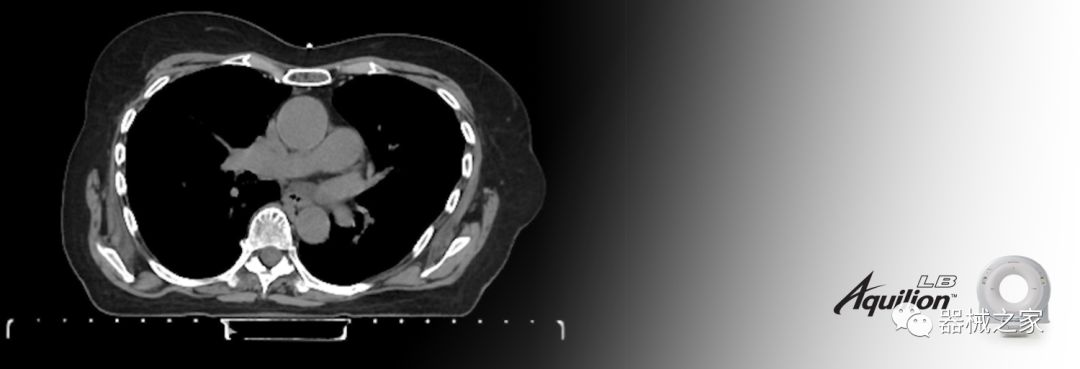

在以患者為中心的放射腫瘤學(xué)領(lǐng)域,計算機斷層掃描(CT)的可訪問性,可重復(fù)性和靈活性至關(guān)重要。為了建立這些價值,佳能醫(yī)療系統(tǒng)美國公司現(xiàn)在正在擴大其放射腫瘤學(xué)CT模擬產(chǎn)品,包括Aquilion Prime SP和Aquilion Lightning 80高級CT系統(tǒng)。除了Aquilion LB之外,Aquilion Prime SP和Aquilion Lightning 80現(xiàn)在還包括放射治療(RT)選項,可為腫瘤學(xué)規(guī)劃提供高質(zhì)量的CT成像和精密工具。

擴展視野(EFOV)可以看到更多的解剖結(jié)構(gòu)。Aquilion LB采用85 cm EFOV,而Aquilion Prime SP和Aquilion Lightning 70采用70 cm EFOV。

Aquilion LB專為滿足腫瘤學(xué)挑戰(zhàn)而設(shè)計,同時優(yōu)先考慮患者護理。Aquilion LB的內(nèi)徑為90 cm,能夠幫助復(fù)雜的患者設(shè)置并提高患者的舒適度。CT模擬定位可以輕松鏡像放射治療定位,更加自信。該系統(tǒng)采用0.5 mm x 16排(32層)PUREViSION探測器技術(shù),70 cm視野,AIDR 3D和SEMAR技術(shù)。